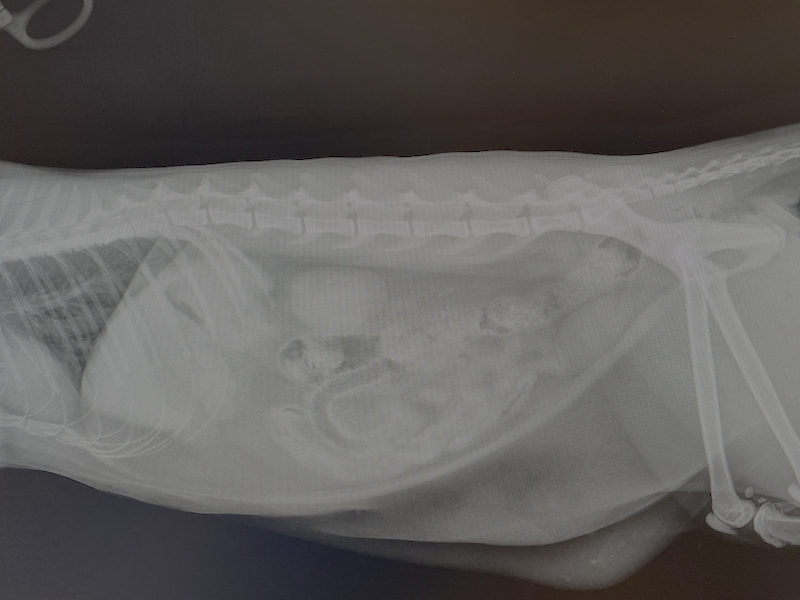

I write this from the veterinary hospital. My one-year-old cat Twiggy ate a dozen hair ties last night while we were at a friend’s house celebrating NYE. Alas, what an omen for 2026. I am almost certain that she’ll be ok. She’s always been our little diva, and now I have the vet bill to prove it.